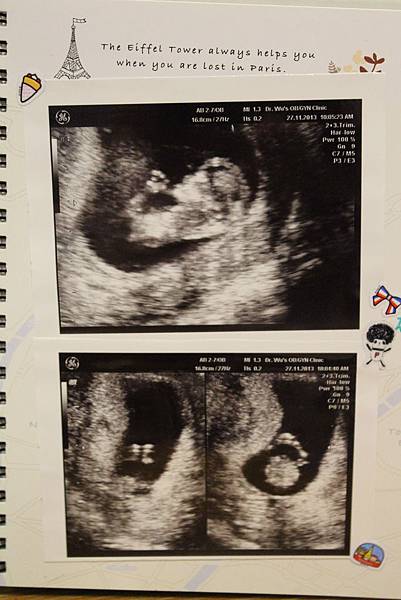

• 【孕期】呼~鬆了一口氣

IMG_3880.JPG

第四次產檢

醫生一樣強調著「頸部透明帶正常」、「手指腳趾正常」、「嘴唇正常」